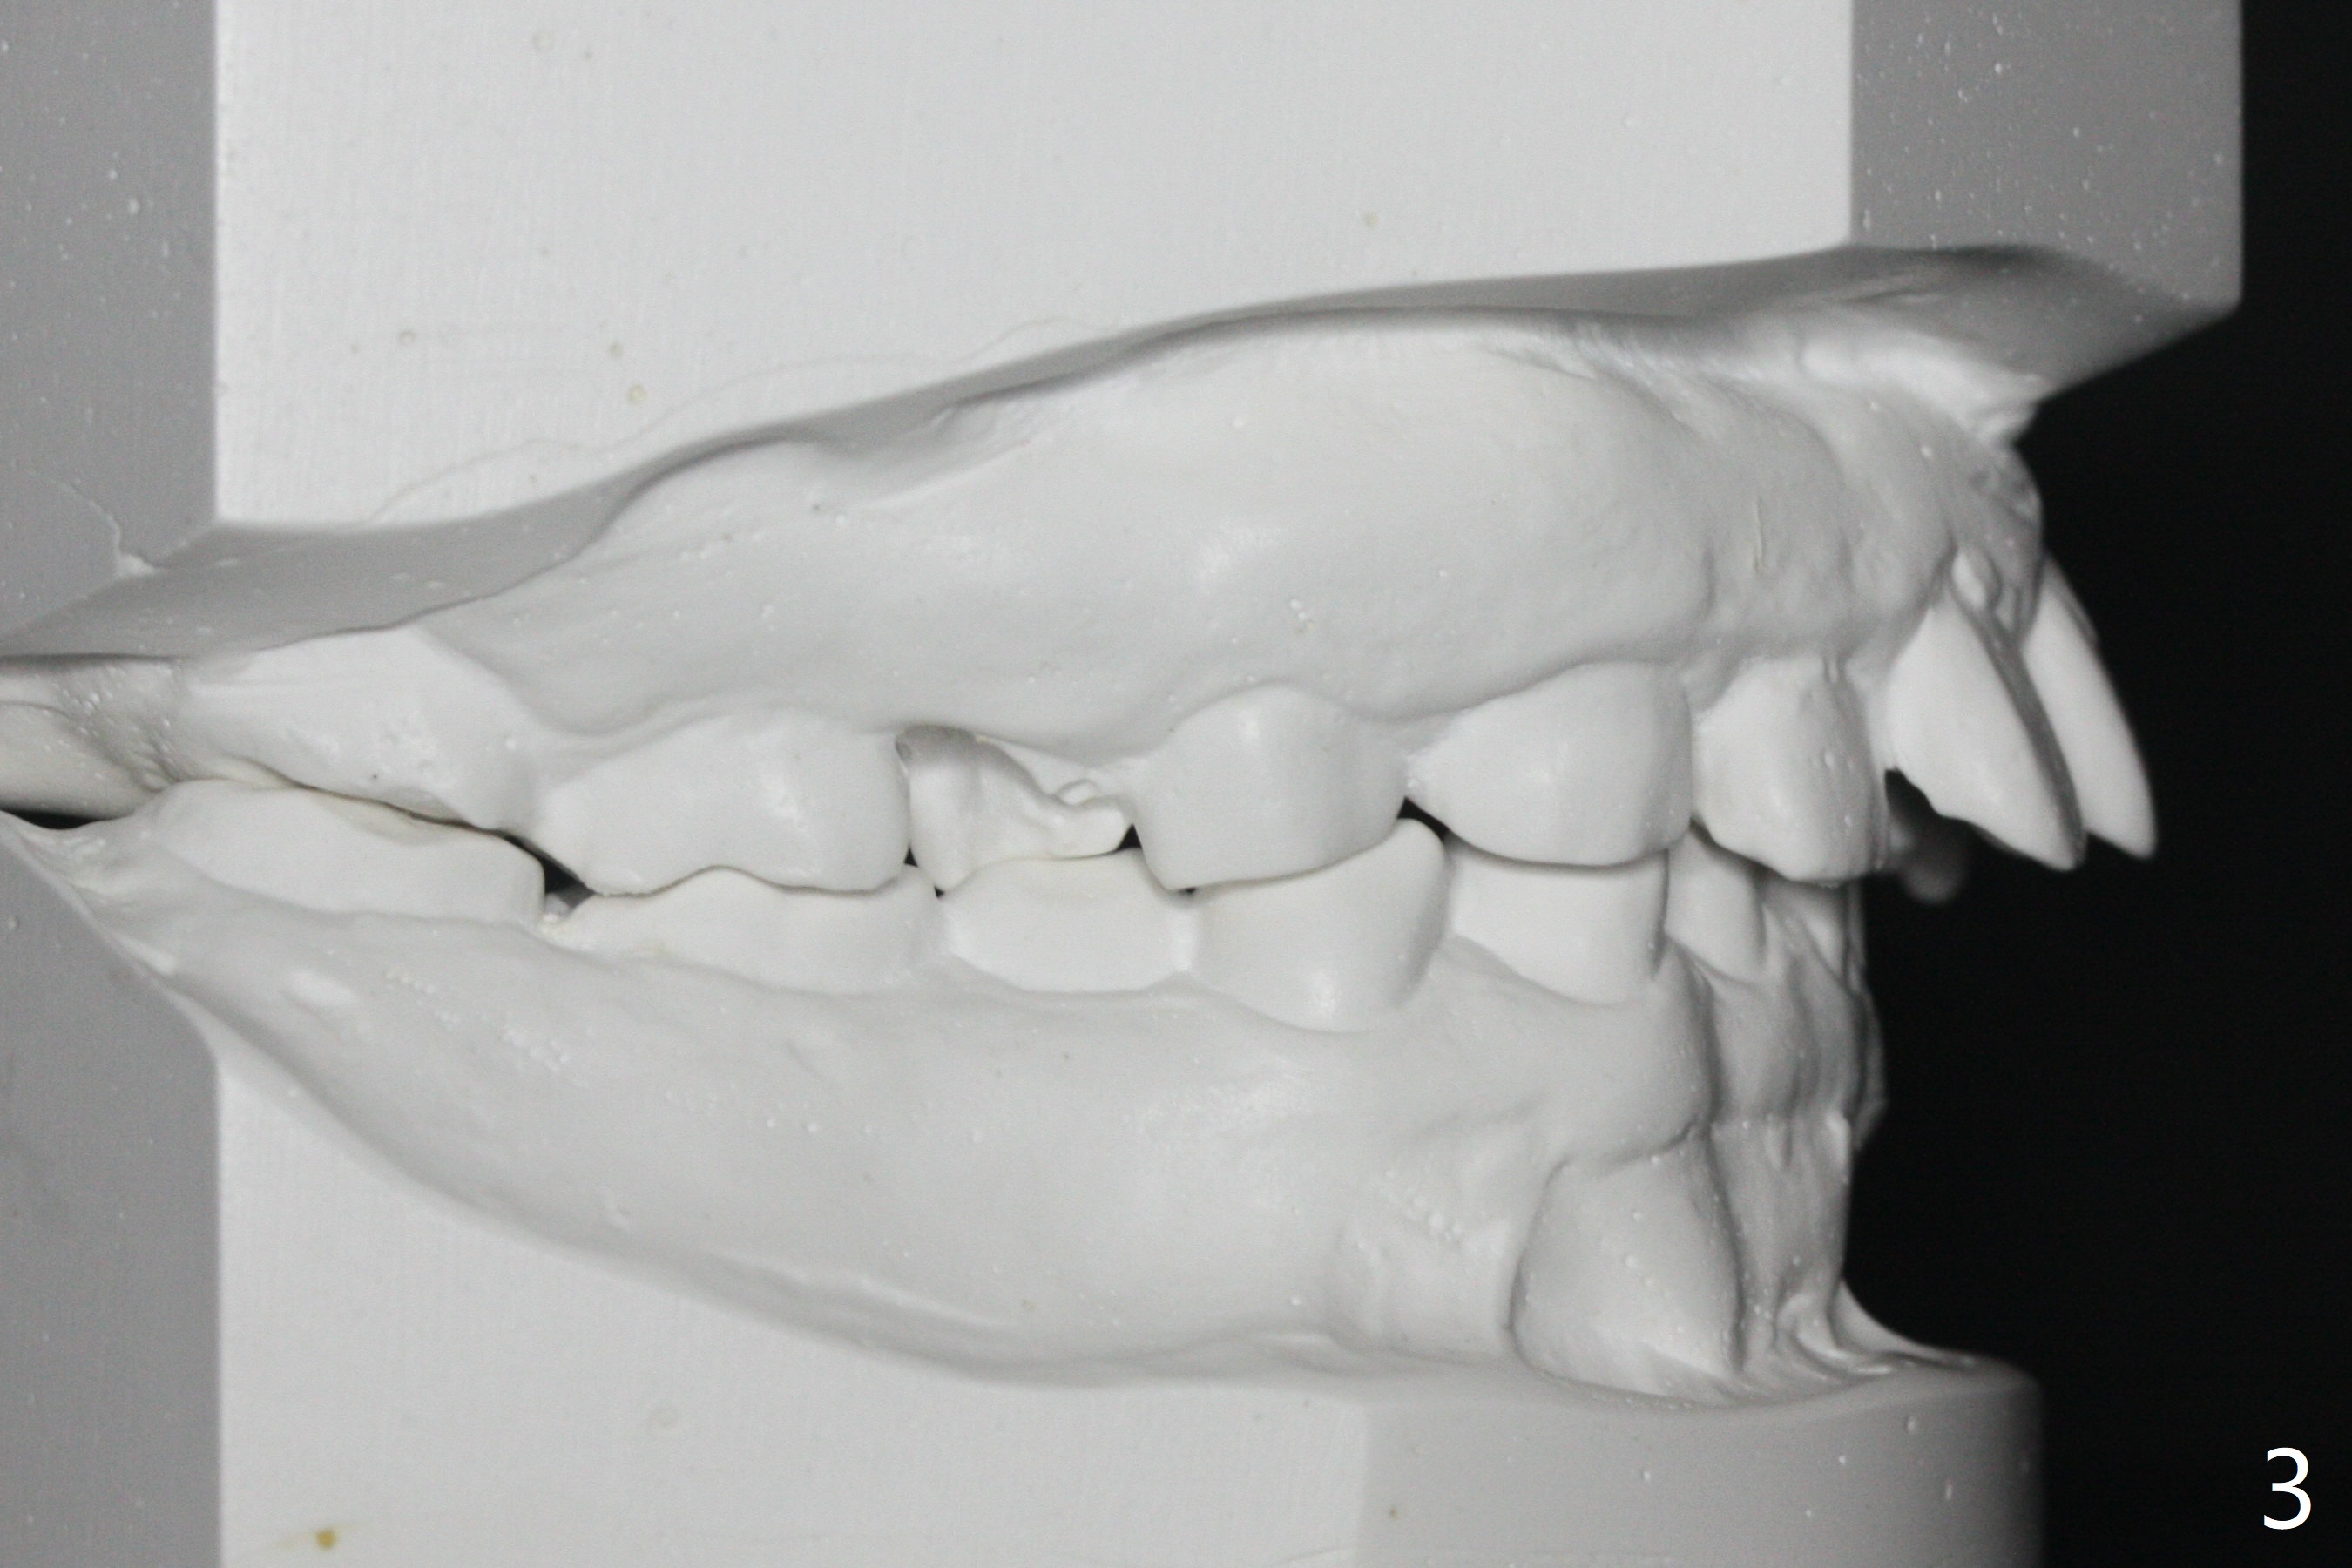

A 32-year-old man has had severe crowding for the last 10 years (Fig.1-5).  He is ready for orthodontic treatment now.  LL5 has been extracted for 4 years (Fig.1 x).  Severe caries at UR5 makes it easy to decide for extraction (Fig.2 x), while it is hard to determine which of the LR bicuspids needs to be extracted because of moderate caries at LR5 and even harder for UL because of caries at UL6,7 (Fig.2 *).

In fact impression for models (Fig.3-7) is taken after UL caries control.  Sedative filling is done at UL1,3 (Fig.6 *) and definitive restoration will be done when crowding resolves.  The defects at UL6,7 (Fig.6 x) is so extensive that after composite molar bands are placed immediately for retention.  Amazingly, there is no symptom after UL6,7 restoration.  Therefore UL4 will be extracted for crowding resolution.  UR 5 (Fig.1-3,6) has been extracted, while LR5 (Fig.2,7) will be.